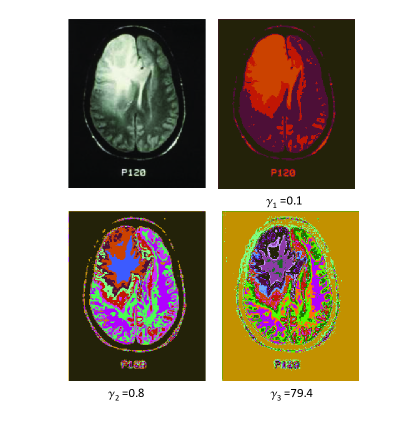

XI.1 Brain Image

XI.1.1 Unweighted graphs

We start the review of the results of our methods by analyzing an unweighted graph (Eq. (1)) for the grey-scale brain image as shown in Fig. 5. We will assign edges between pixels only if the intensity difference is less than the threshold as denoted in panel (a) of Fig. 5. The algorithm uses Eq. (1) to solve for a range of resolution parameters in the interval . In the particular case in Fig. 5, and . There are two more input parameters that are needed in our algorithm: the number of independent replicas that will be solved at each tested resolution and the number of trials per replica . We use and in Fig. 5 respectively.

As noted earlier (see Section V), for each replica, we select the lowest energy solution among the trials. The replicas are generated by reordering the “symmetric” initialized state of one node per community. We then use the information based measures (i.e., or ) to determine the multiresolution structure.

The plots of , and as a function of in Fig. 5 exhibit non-trivial behaviors. Extrema in and correspond to jumps in the number of communities . In the low region, i.e., , the number of communities is stable. However, when , the number of communities sharply increase. This indicates that the structure changes rapidly as the resolution varies. There are three prominent peaks in the (variation of information) curve. We show the corresponding images at these resolutions, that is in panel(b) in Fig. 5. These corresponding segmented images show more and more sophisticated structures. The lower right image at a resolution of shows the information in detail. Different colors in the image correspond to different clusters. There are, at least, five contours surrounding the tumor, that denote the degree by which the tissue was pushed by the tumor. The lower left image at the resolution is less detailed than the one on the right. Nevertheless, it retains the details surrounding the tumor. If we further decrease , the upper right image at the resolution will not keep the details of the tumor boundary, only the rough location of the tumor. Thus, neither too large nor too small resolutions are appropriate for tumor detection in this image. The resolution around is the most suitable in this case. This is in accord with our general found maxim in Section IX concerning a value of . We re-iterate that, in general, the optimal value of is found by Eq.(21) (an example of which is manifest in the information theory plateaus discussed in Section VII.2). In Section XI.7, we will discuss, in depth, how the optimal values of may be determined in (weighted) example systems.